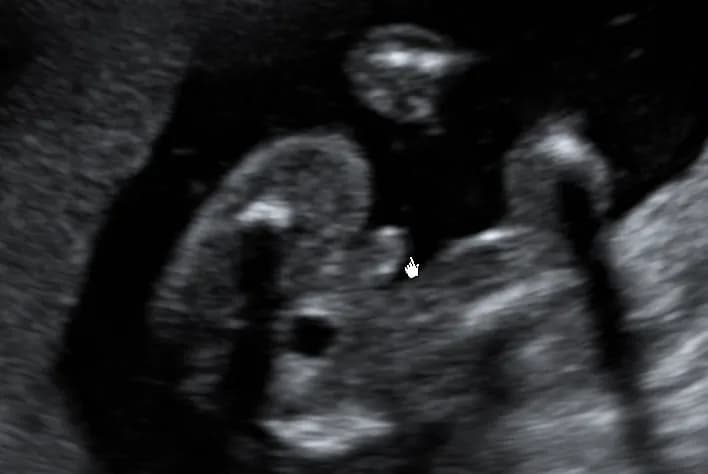

Badanie USG w 16 tygodniu ciąży to moment, gdy rodzice mogą po raz pierwszy zobaczyć swoje dziecko w bardziej szczegółowy sposób. Lekarz ocenia rozwój płodu, sprawdza narządy wewnętrzne i może spróbować określić płeć. Jednak nie zawsze jest to łatwe.

Dokładność badania zależy od kilku czynników. Pozycja dziecka ma kluczowe znaczenie – jeśli maluch jest ułożony w niewygodny sposób, płeć może być trudna do rozpoznania. Jakość sprzętu USG również odgrywa rolę, podobnie jak doświadczenie lekarza prowadzącego badanie.